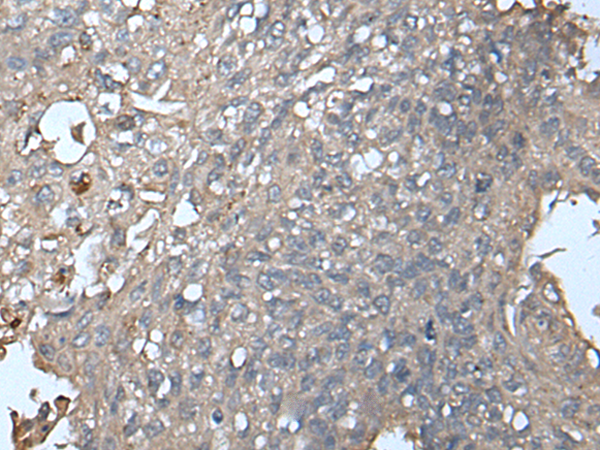

IHC positive control: |

Human liver cancer and Human lung cancer |